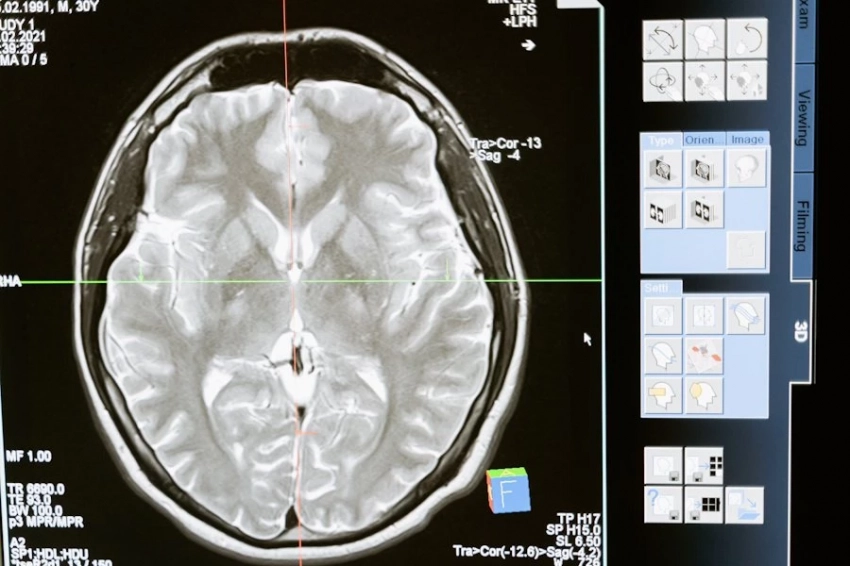

Ученые обнаружили связь между накоплением железа и разрушением клеток мозга при деменции

В результате исследования, проведенного учёными из Университета здравоохранения и науки штата Орегон, стало известно, что микроглия разрушается, если организм накопил слишком много железа. Иммунные клетки мозга, на которые негативно влияет железо, контролируют устранение клеточных отходов. Они также удаляют аномальные клетки, которые образуются в мозге. Микроглия занимается выведением миелина, то есть защитной оболочки нервных волокон. Представители науки исследовали образцы тканей мозга, которые принадлежали людям с деменцией. Когда устраняется миелин, богатый железом, происходит разрушение микроглии. Дегенеративные процессы в микроглии, как считают учёные, играют самую важную роль в том, что у больных деменцией и болезнью Альцгеймера резко ухудшаются когнитивные функции.